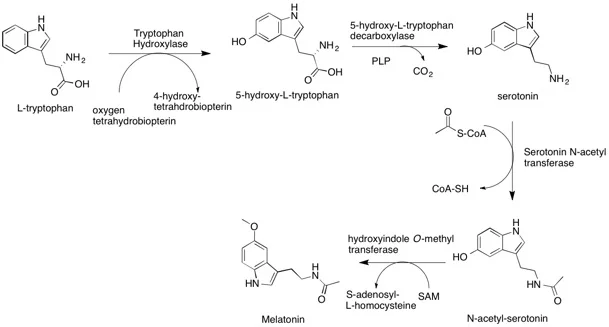

- Melatonin is derived from the amino acid tyrptophan. R

- Tryptophan is converted to serotonin by AANAT (arylalkylamine N-acetyltransferase), which converts serotonin to N-acetylserotonin. R

- ASMT (Acetylserotonin O-methyltransferase) is an ezyme that is encoded by the ASMT gene and that catalyzes the final reaction in melatonin biosynthesis, converting Normelatonin to melatonin. R

- BH4 reacts with oxygen and the active site of iron of tryptophan hydroxylase.

- It may either:

- There is a transfer of 1 electron of pterin to O2, creating superoxide.

- The superoxide combines with the pterin radical to create 4a-peroxypterin.

- Along with the active site iron (II), it creates iron-peroxypterin intermediate, directly transfering an O atom to Fe.

OR - O2 produces iron (III) superoxide by reacting with the active site iron (II).

- Iron (III) superoxide reacts with pterin to create an iron-peroxypterin intermediate.

- There is a double bond of iron oxide (from the iron-peroxypterin) to give a carbocation at the C5 position of the indole ring.

- Hydrogen loses 1 of its 2 atoms to create 5-hydroxy-L-tryptophan. R

- PLP along with a decarboxylase removes CO2 from 5-hydroxy-L-tryptophan to create 5-hydroxytryptamine. R

- PLP forms an imine with 5-hydroxytryptamine.

- The pyridine amine breaks the C-C bond, releasing CO2 by pronating and acting as an electron sink.

- By pronating the amine from tryptophan, it restores the aromaticity of the pyridine ring.

- The imine is then hydrolyzed to produce 5-hydroxytryptamine and PLP. R

- His122 of serotonin N-acetyl transferase catalyzes 5-hydroxytryptamine.

- This allows a lone pair on the amine to attack acetyl-CoA, forming a tetraherdral intermediate.

- The thiol from coenzyme A leaves allowing N-acetyl-serotonin to form. R

- SAM (S-adenosyl methionine) methylates N-acetyl-serotonin at the hydroxyl position producing SAH (S-adenosyl homocysteine) and melatonin. R